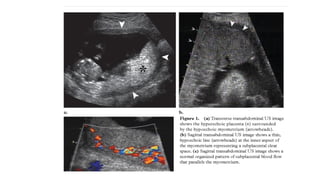

• DIAGNOSIS

Ultrasonography should be done by a competent in

cases of suspected placenta accrete.

Sensitivity of ultrasound imaging around 90% with

negative predictive values ranging between 95%

and 98%

Grey scale signs Colour Doppler Signs

Loss of retroplacental

hypoechoic zone

Dilated vascular

channels with diffuse

lacunar flow

Progressive thinning of

the retroplacental

(myometrium) < 2mm

Irregular vascular lakes

with focal lacunar flow

Multiple placental lakes Hypervascularity linking

placenta to bladder

Thinning of the uterine

serosa- bladder wall

complex (percreta)

Dilated, vascular

channels with pulsatile

venous flow over cervix

Elevation of tissue

beyond the uterine

serosa- extension of the

placenta beyond the

myometrium (percreta)

Poor vascularity at sites

of loss hypoechoic zone